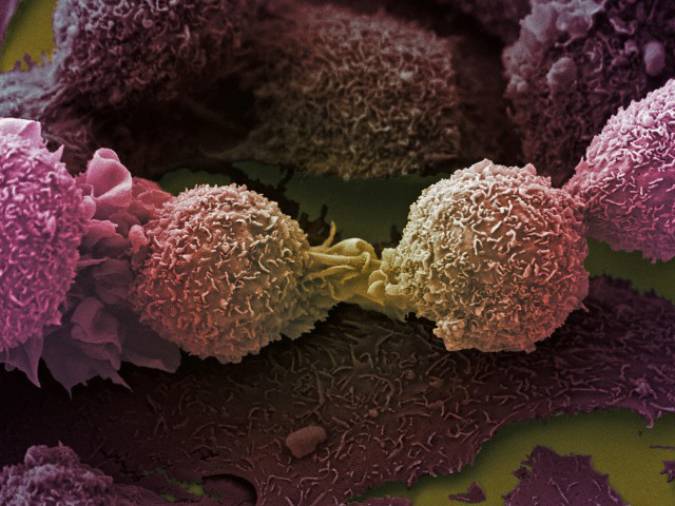

Tumori: nel 66% dei casi non sono ereditari nè dipendono da comportamenti sbagliati

Maria Sole Bosaia

Una ricerca americana ha evidenziato che una buona percentuale di alcuni tipi di tumori sono casuali, non dipendono da fattori genetici o ambientali.